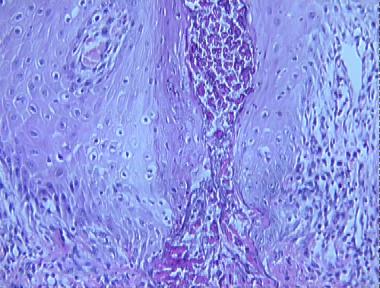

elastosis perforans serpiginosa

Histologic Features